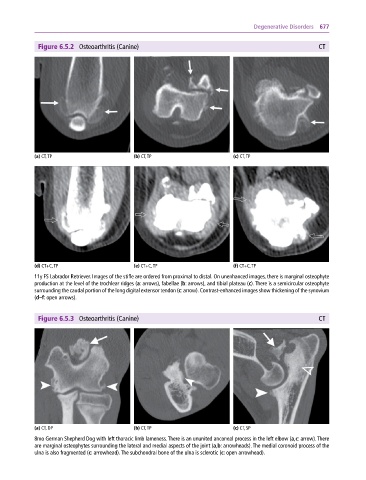

Figure 6.5.2 Osteoarthritis (Canine) CT

(a) CT, TP (b) CT, TP (c) CT, TP

(d) CT+C, TP (e) CT+C, TP (f) CT+C, TP

11y FS Labrador Retriever. Images of the stifle are ordered from proximal to distal. On unenhanced images, there is marginal osteophyte

production at the level of the trochlear ridges (a: arrows), fabellae (b: arrows), and tibial plateau (c). There is a semicircular osteophyte

surrounding the caudal portion of the long digital extensor tendon (c: arrow). Contrast‐enhanced images show thickening of the synovium

(d–f: open arrows).

Figure 6.5.3 Osteoarthritis (Canine) CT

(a) CT, DP (b) CT, TP (c) CT, SP

8mo German Shepherd Dog with left thoracic limb lameness. There is an ununited anconeal process in the left elbow (a,c: arrow). There

are marginal osteophytes surrounding the lateral and medial aspects of the joint (a,b: arrowheads). The medial coronoid process of the

ulna is also fragmented (c: arrowhead). The subchondral bone of the ulna is sclerotic (c: open arrowhead).